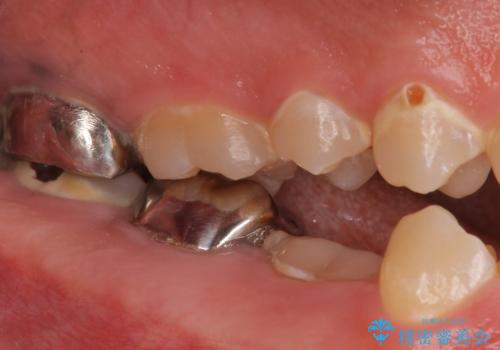

奥歯は十分な歯の高さがなかったため、クラウンをかぶせる前に歯周外科治療で歯の高さを出しています。

歯科に通うようになってから磨き残しの状態も改善されていきました。